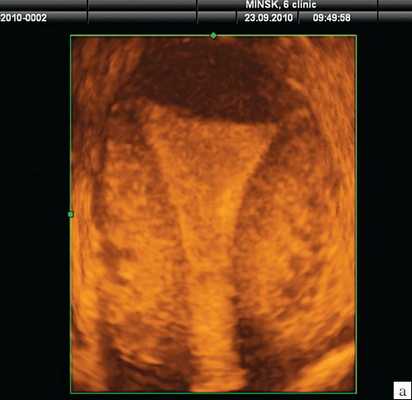

Разнообразие форм и наличие осложнений требует при ведении женщин с ВМС визуального контроля корректной установки и расположения средств в полости матки. Основным методом диагностики на сегодняшний день является ультразвуковое исследование (УЗИ). Классическое двумерное УЗИ (2D-УЗИ) позволяет оценить нахождение и расположение стержня ВМС в полости матки [2]. В то же время для полной оценки соотношения ВМС и полости матки с визуализацией расположения плечиков требуется 3D-УЗИ с реконструкцией коронального среза матки [3, 4]. Кроме того, этот метод позволяет оценить и разновидность установленного средства. N.K. Kerr и соавт. [5] утверждают, что 3D-УЗИ следует использовать во всех случаях, когда проводится оценка ВМС.

На рис. 2 отражена картина различных ВМС на среднесагиттальном срезе матки при 2D-УЗИ. Для всех Т-образных форм ВМС (включая Мирену) и Multiload стандартной картиной является визуализация гиперэхогенной линейной структуры в проекции полости (рис. 2а). В отличие от Т-образных, Multiload при исследовании в парасагиттальном сечении дает дополнительную специфическую ультразвуковую картину в виде 3-4 продольно расположенных одинаковых гиперэхогенных включений (рис. 2в). Также характерную картину на сагиттальном срезе дают кольцевидные ВМС в виде проксимальной короткой линейной структуры и дистальной отдельной точечной (рис. 2б) и петля Липпеса в виде 4-5 отдельных эхогенных фрагментов (рис. 2г). Кольцевидные ВМС и петля Липпеса в настоящее время практически вышли из употребления.